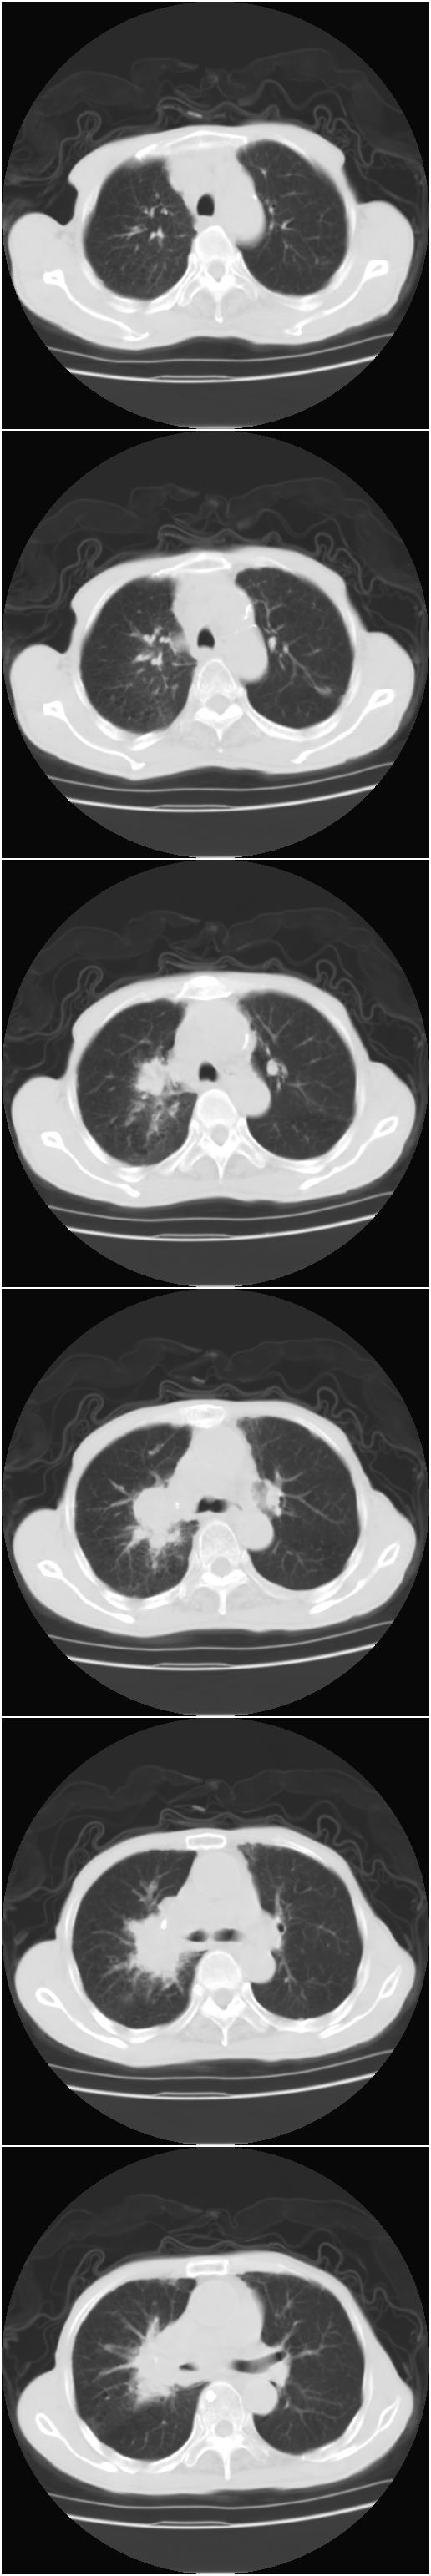

标题: CT12024:男,77岁。咳嗽两月余,气喘一月,13年前岑作贲门 [打印本页]

标题: CT12024:男,77岁。咳嗽两月余,气喘一月,13年前岑作贲门

1、右侧中心型肺癌,右肺门,纵隔淋巴结转移可能性大。

2、贲门癌术后所见。

右侧中心型肺癌,右肺门,纵隔淋巴结转移。

右中心型肺癌 纵隔淋巴结转移

右侧中央型肺癌伴右肺门及纵隔淋巴结转移.

1 右肺中心型肺癌伴右肺门及纵隔淋巴结转移.

2  左肺贲门癌术后改变.

1)考虑为:右侧中心型肺癌并右肺门及纵隔淋巴结转移。2)贲门癌术后改变。